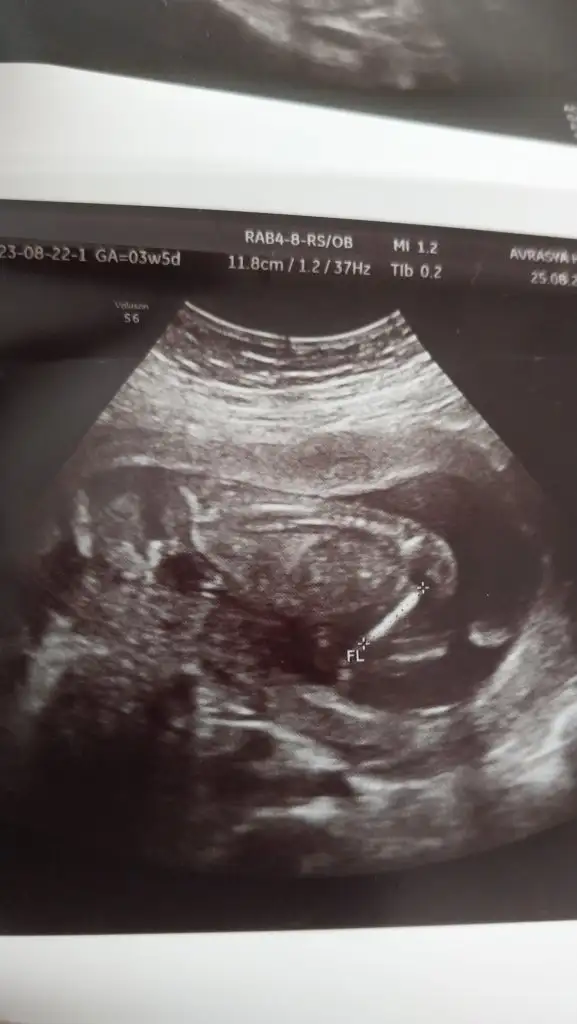

Merhaba lar hanımlar ilk 2 resim 11 haftalikken diğer resimlerde 15 haftalikken banada tahminde bulunurmusunuz